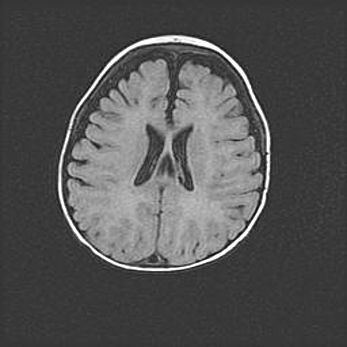

Лейкомаляция с кистозно-глиозной дегенерацией головного мозга.

Возраст: 2 месяца 25 дней

Вес: 6400 г

Окружность головы: 40 см

Срок гестации: 41 неделя

Лейкомаляцию относят к ишемически-гипоксическим повреждениям головного мозга, диагностируемым у новорожденных. При лейкомаляции в головном мозге обнаруживают очаги некроза, возникшие после тяжелой гипоксии и нарушения кровотока. В процессе морфогенеза очаги проходят три стадии: 1) развития некроза, 2) резорбции и 3) формирования глиозного рубца или кисты. Перивентрикулярная лейкомаляция (ПЛ) встречается примерно в 12% случаев среди новорожденных, обычно – у недоношенных детей, причем, частота ее зависит от массы, с которой младенец появился на свет. Наибольшее число малышей страдает лейкомаляцией, если масса при рождении 1500-2500 г.